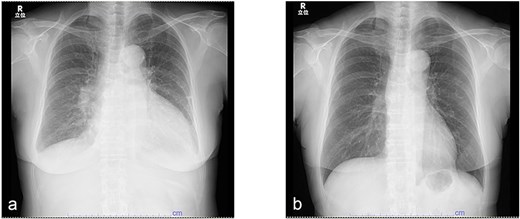

A 62-year-old woman presented with a 3-month history of progressive fatigue. She had no significant medical history and denied fever, flank pain, or urinary symptoms. On admission, her blood pressure was 182/133 mmHg, heart rate 120 bpm, and SpO₂ 97%. Laboratory testing revealed a markedly elevated brain natriuretic peptide (BNP) level of 12 000 pg/mL, while inflammatory markers were within normal ranges (C-reactive protein, 0.2 mg/dL; procalcitonin, 0.03 ng/mL). Serum creatinine was mildly elevated at 1.44 mg/dL. Chest radiography demonstrated cardiomegaly with a cardiothoracic ratio (CTR) of 61% (Fig. 1a).

Serial changes in chest radiography. (a) Chest radiograph at initial presentation showing cardiomegaly with a cardiothoracic ratio of 61%. (b) Follow-up chest radiograph after 3 months demonstrating marked improvement in cardiac enlargement.

After urinary decompression, heart failure symptoms rapidly improved. At 3 months, BNP had decreased to 212 pg/mL, and LVEF had recovered to 73% (Fig. 2b). The CTR normalized, and body weight decreased by 9.2 kg (Fig. 1b). No infectious complications occurred, and antibiotics were not required. After stabilization of cardiac function, endoscopic treatment of the left ureteral stone was performed 4 months after presentation, achieving stone-free status. The right ureteral stone remained under treatment at the time of reporting; however, bilateral PCN drainage was maintained, and no recurrence of cardiac dysfunction was observed.